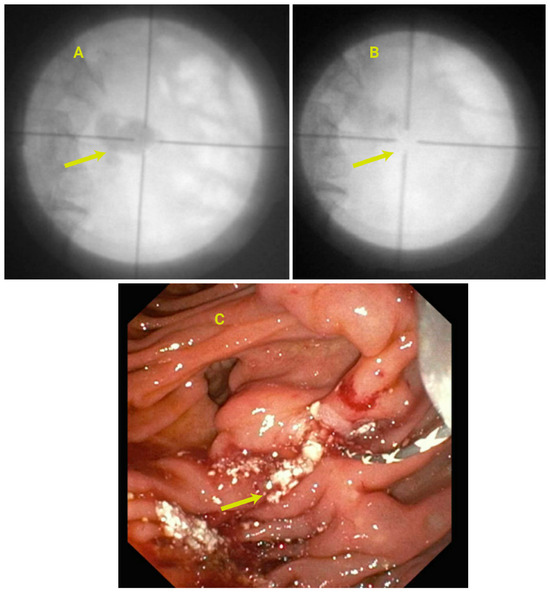

3.15. Endoscopic Management of PD Calculi and Strictures

3.16. Role of EUS in the Management of CP